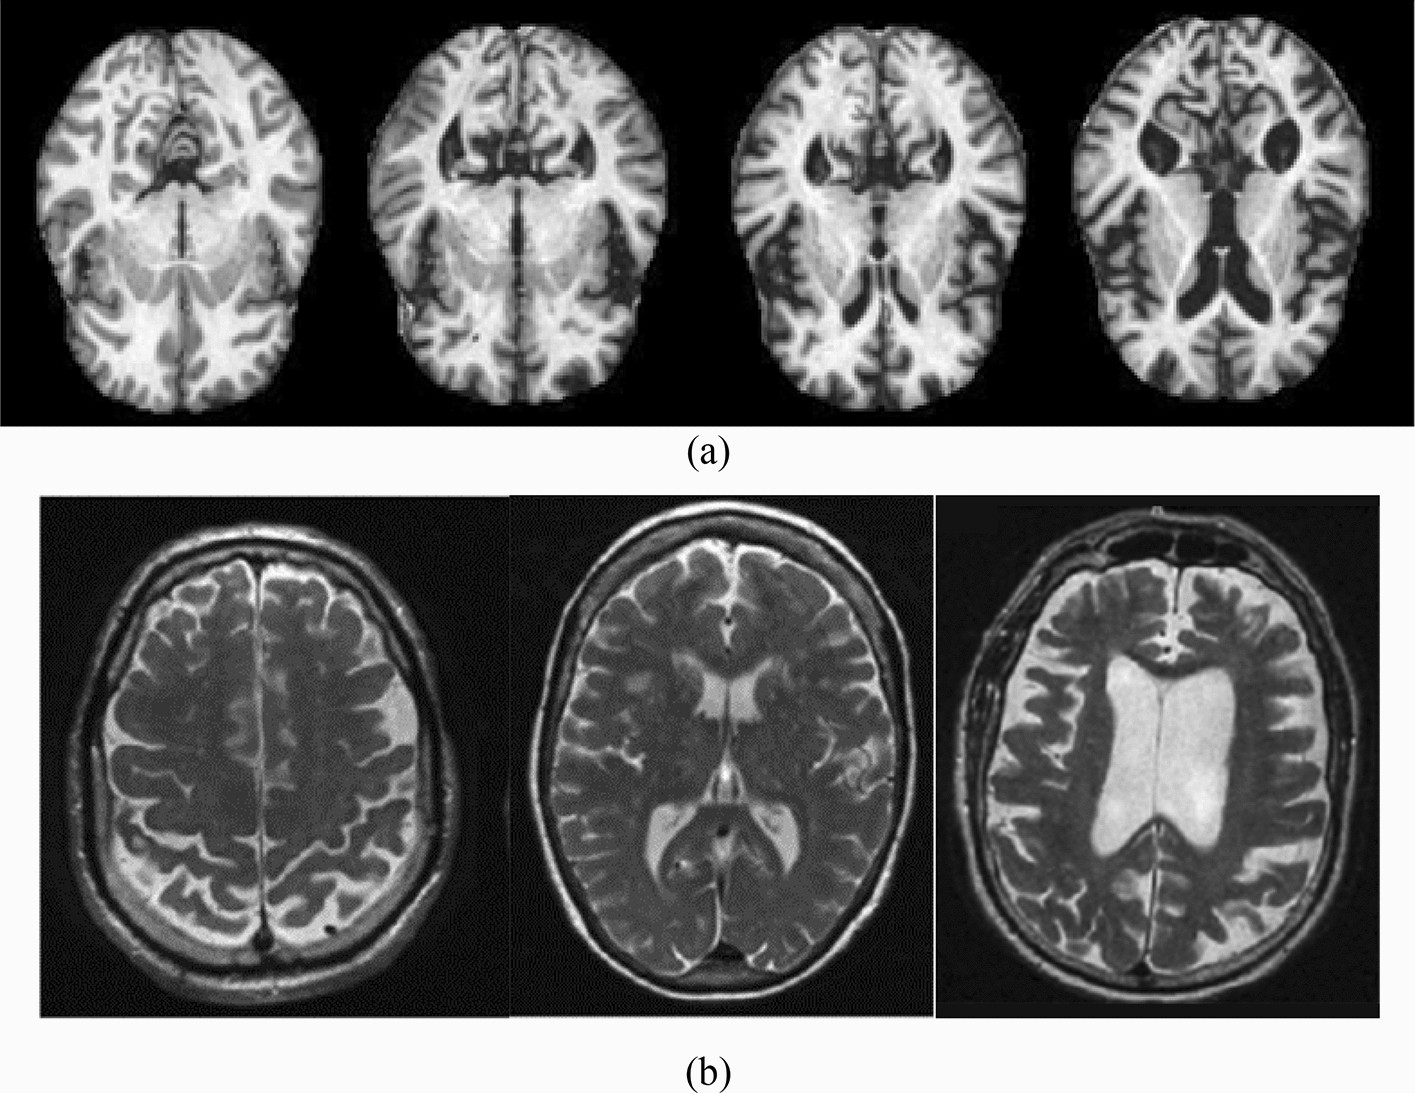

The differences in the area of CSF in (a) the kaggle dataset the images from left to write as no dementia, very mild dementia, mild dementia and moderate dementia (b) the ADNI datasets the images from left to right as CN, MCI and AD.